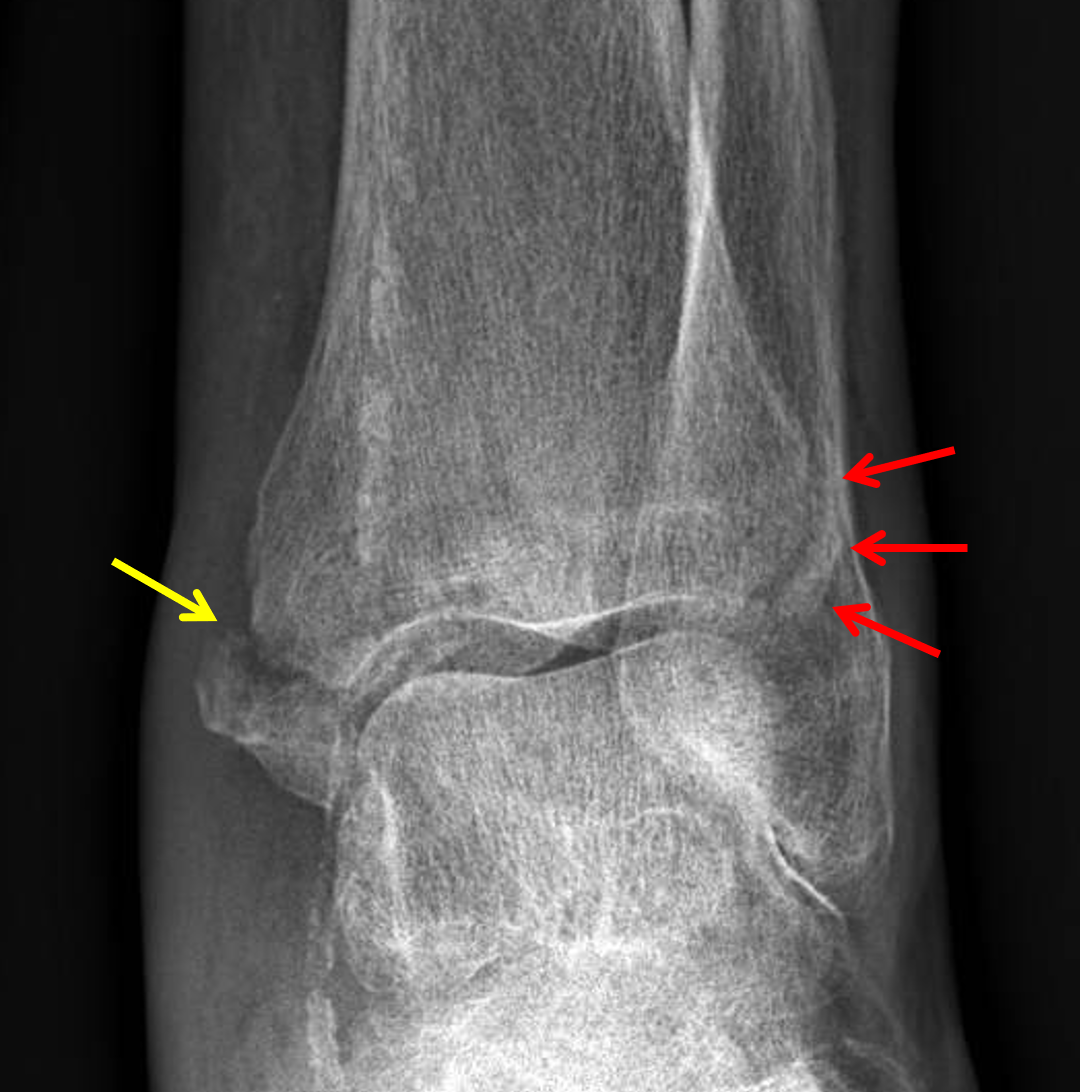

CaseStacks.com โ€” Case #11 โ€” Anterior-inferior tibiofibular ...

CaseStacks.com โ€” Case #11 โ€” Anterior-inferior tibiofibular ... from www.casestacks.com

These avulsion injuries predominantly occur in athletic males as the tibial physis begins. Avulsion fracture of tibial tuberosity radiology. Since these fractures occur at or near skeletal maturity, growth disturbances are not seen.

Fracture through the small distal portion of the tibial tuberosity. Tibial tuberosity avulsion fractures are rare adolescent injuries with a reported incidence ranging from 0.4% to 2.7% 1. The lesion was treated with surgical reduction and internal fixation. Displaced tibial tuberosity fractures are typically treated with open reduction and internal fixation. Surgical intervention consisted of an open reduction, internal fixation performed that. The mason classification is used to classify radial head fractures and is useful when assessing further treatment options 1 2. Tibial tuberosity fractures are infrequent fractures affecting physically active adolescents. Avulsion fracture of the tibial tuberosity is an infrequent injury in adolescents and an extremely rare occurrence in adults. The tuberosity of the tibia or tibial tuberosity or tibial tubercle is an elevation on the proximal, anterior aspect of the tibia, just below where the anterior surfaces of the lateral and medial tibial condyles end. The fracture of tibial tuberosity is a rare lesion and still more unusual in adults. Splits epiphysis of the tuberosity from the epiphysis of the proximal tibia. Avulsion fracture of tibial tuberosity radiology. Deschenes pt ms ocs radiology for the orthopedic. The tibial tuberosity is a substantial upside down triangular region under the site of junction in the middle of the two condyles, on the anterior part of the tibia. Tibial tuberosity avulsion fractures are uncommon. The purpose of this study was to present a rare case of tibial tuberosity avulsion fracture in an adult, the treatment performed, and the challenges faced. An activity that fractures the tuberosity of the tibia in a child or adolescent often results instead in a patellar tendon injury in an adult.